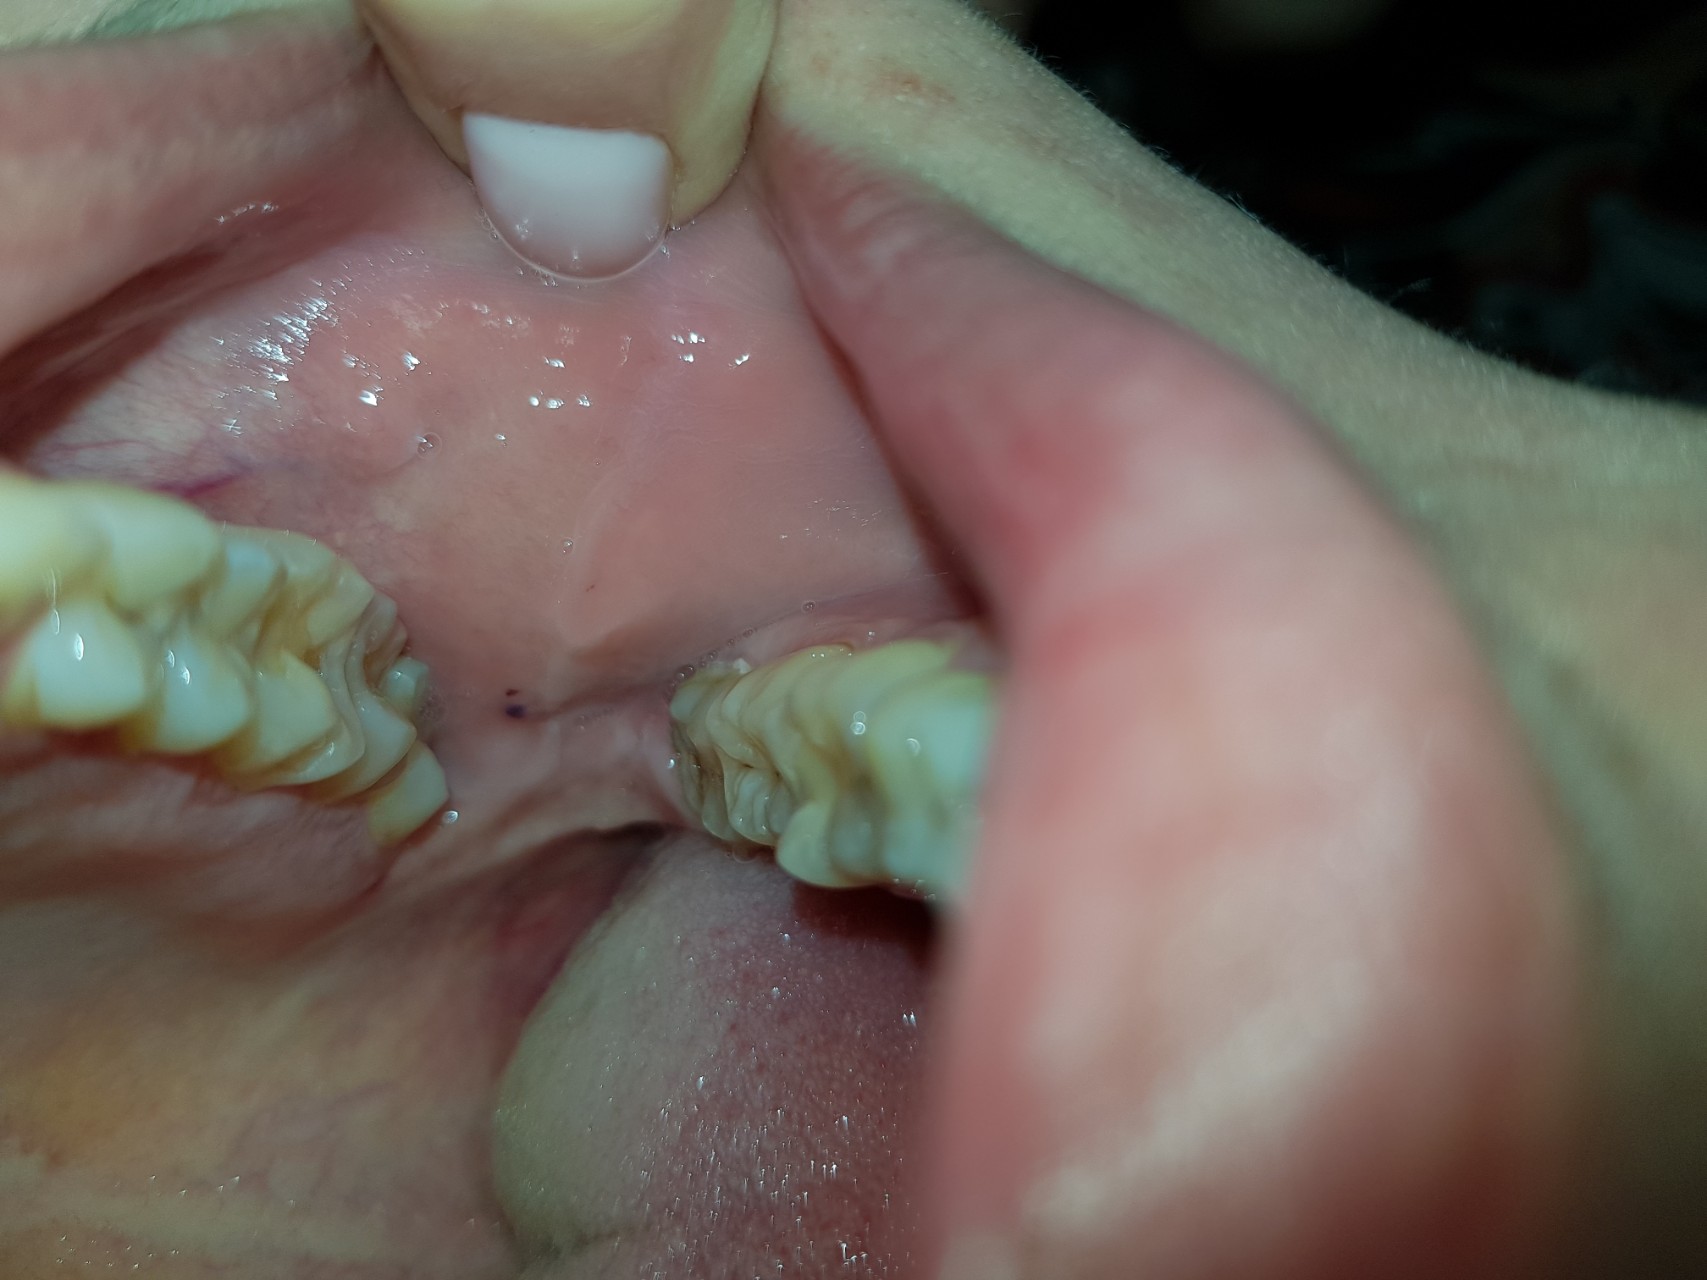

Здравствуйте, около 2 месяцев назад на щеке возле зуба мудрости появилось пятно, через несколько дней показалось, что оно затягивается и я о нем забыла, сегодня случайно заметила, что оно никуда не делось. Скажите пожалуйста, что это может быть? Это не онкология?

Это кровоподтек из-за травмы зубами. Пришлите повторно фото через неделю, к этому времени все должно пройти.